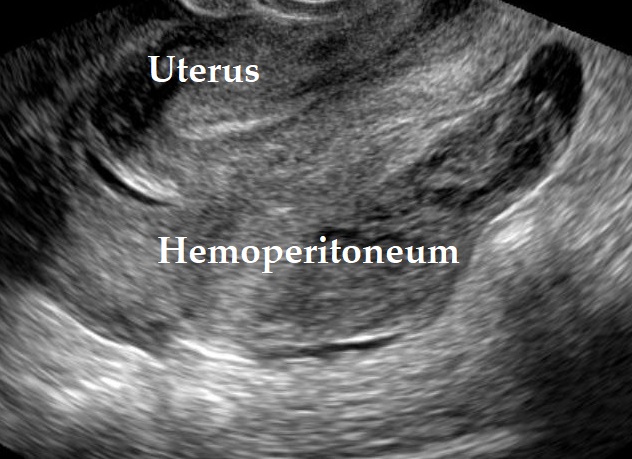

Our image depicts hemoperitoneum in a case of a ruptured corpus luteum cyst after sexual intercourse. Note the blood clots inside the pouch of douglas.

Women of childbearing age presenting with hemoperitoneum of gynecological origin may have ectopic pregnancy, ruptured corpus luteum cyst, uterine rupture, endometriosis, or ruptured hydro-/pyosalpinx.